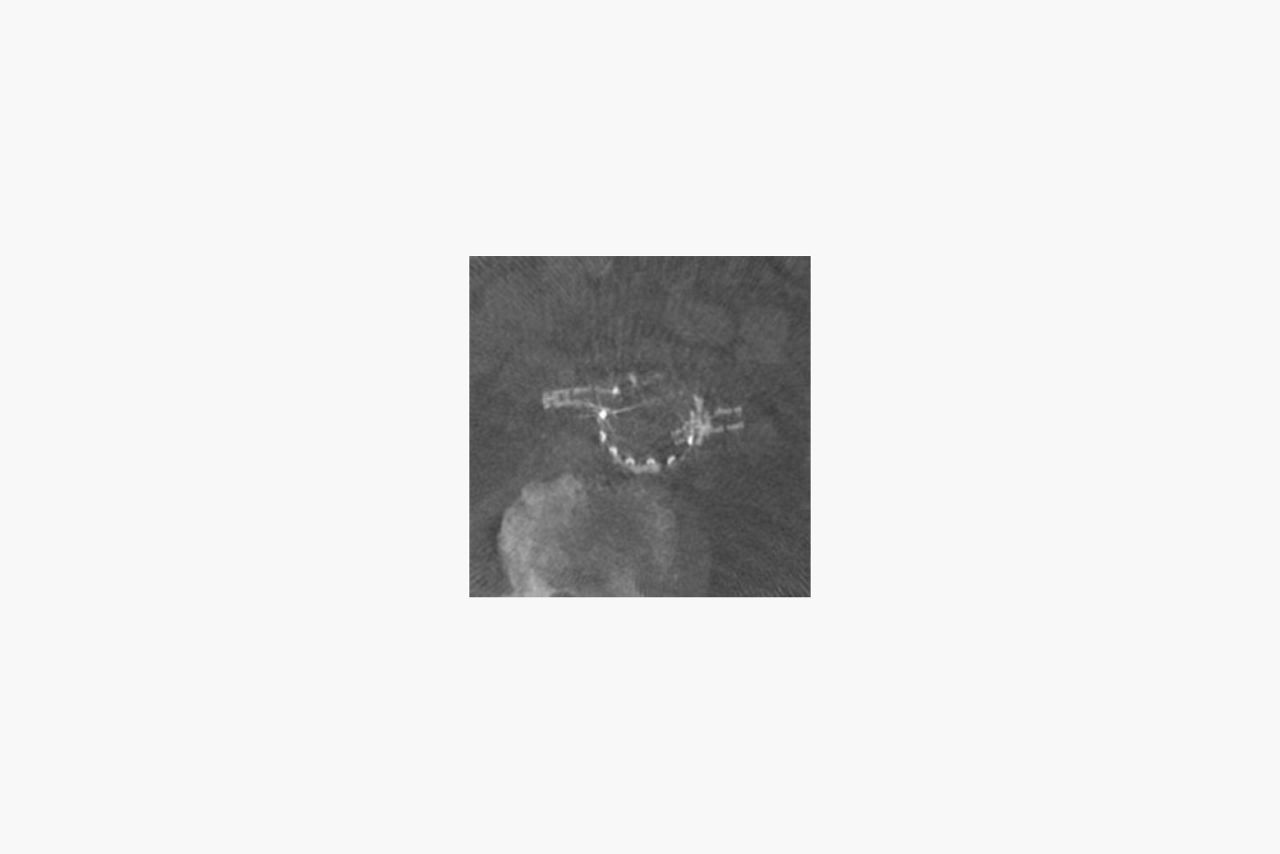

Reduced radiation dose

Perform standard and complex EVAR procedures with reduced radiation

Reduced radiation dose

Perform standard and complex EVAR procedures with reduced radiation